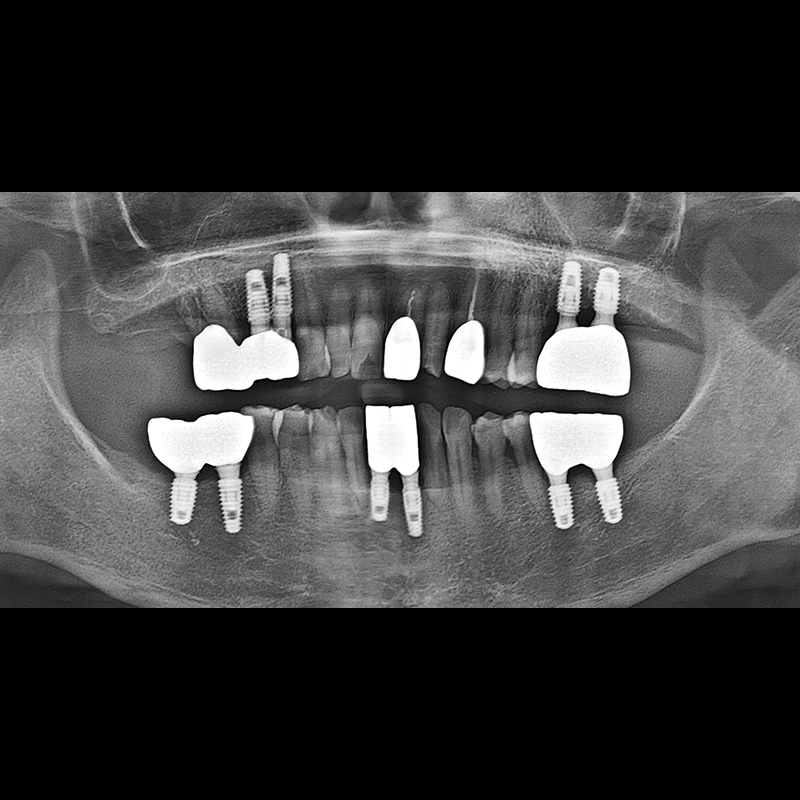

BEFORE AFTER

インプラント手術事例 2025.05.30

欠損した歯の部分と、生かしにくい歯の位置にインプラントを植立しました。